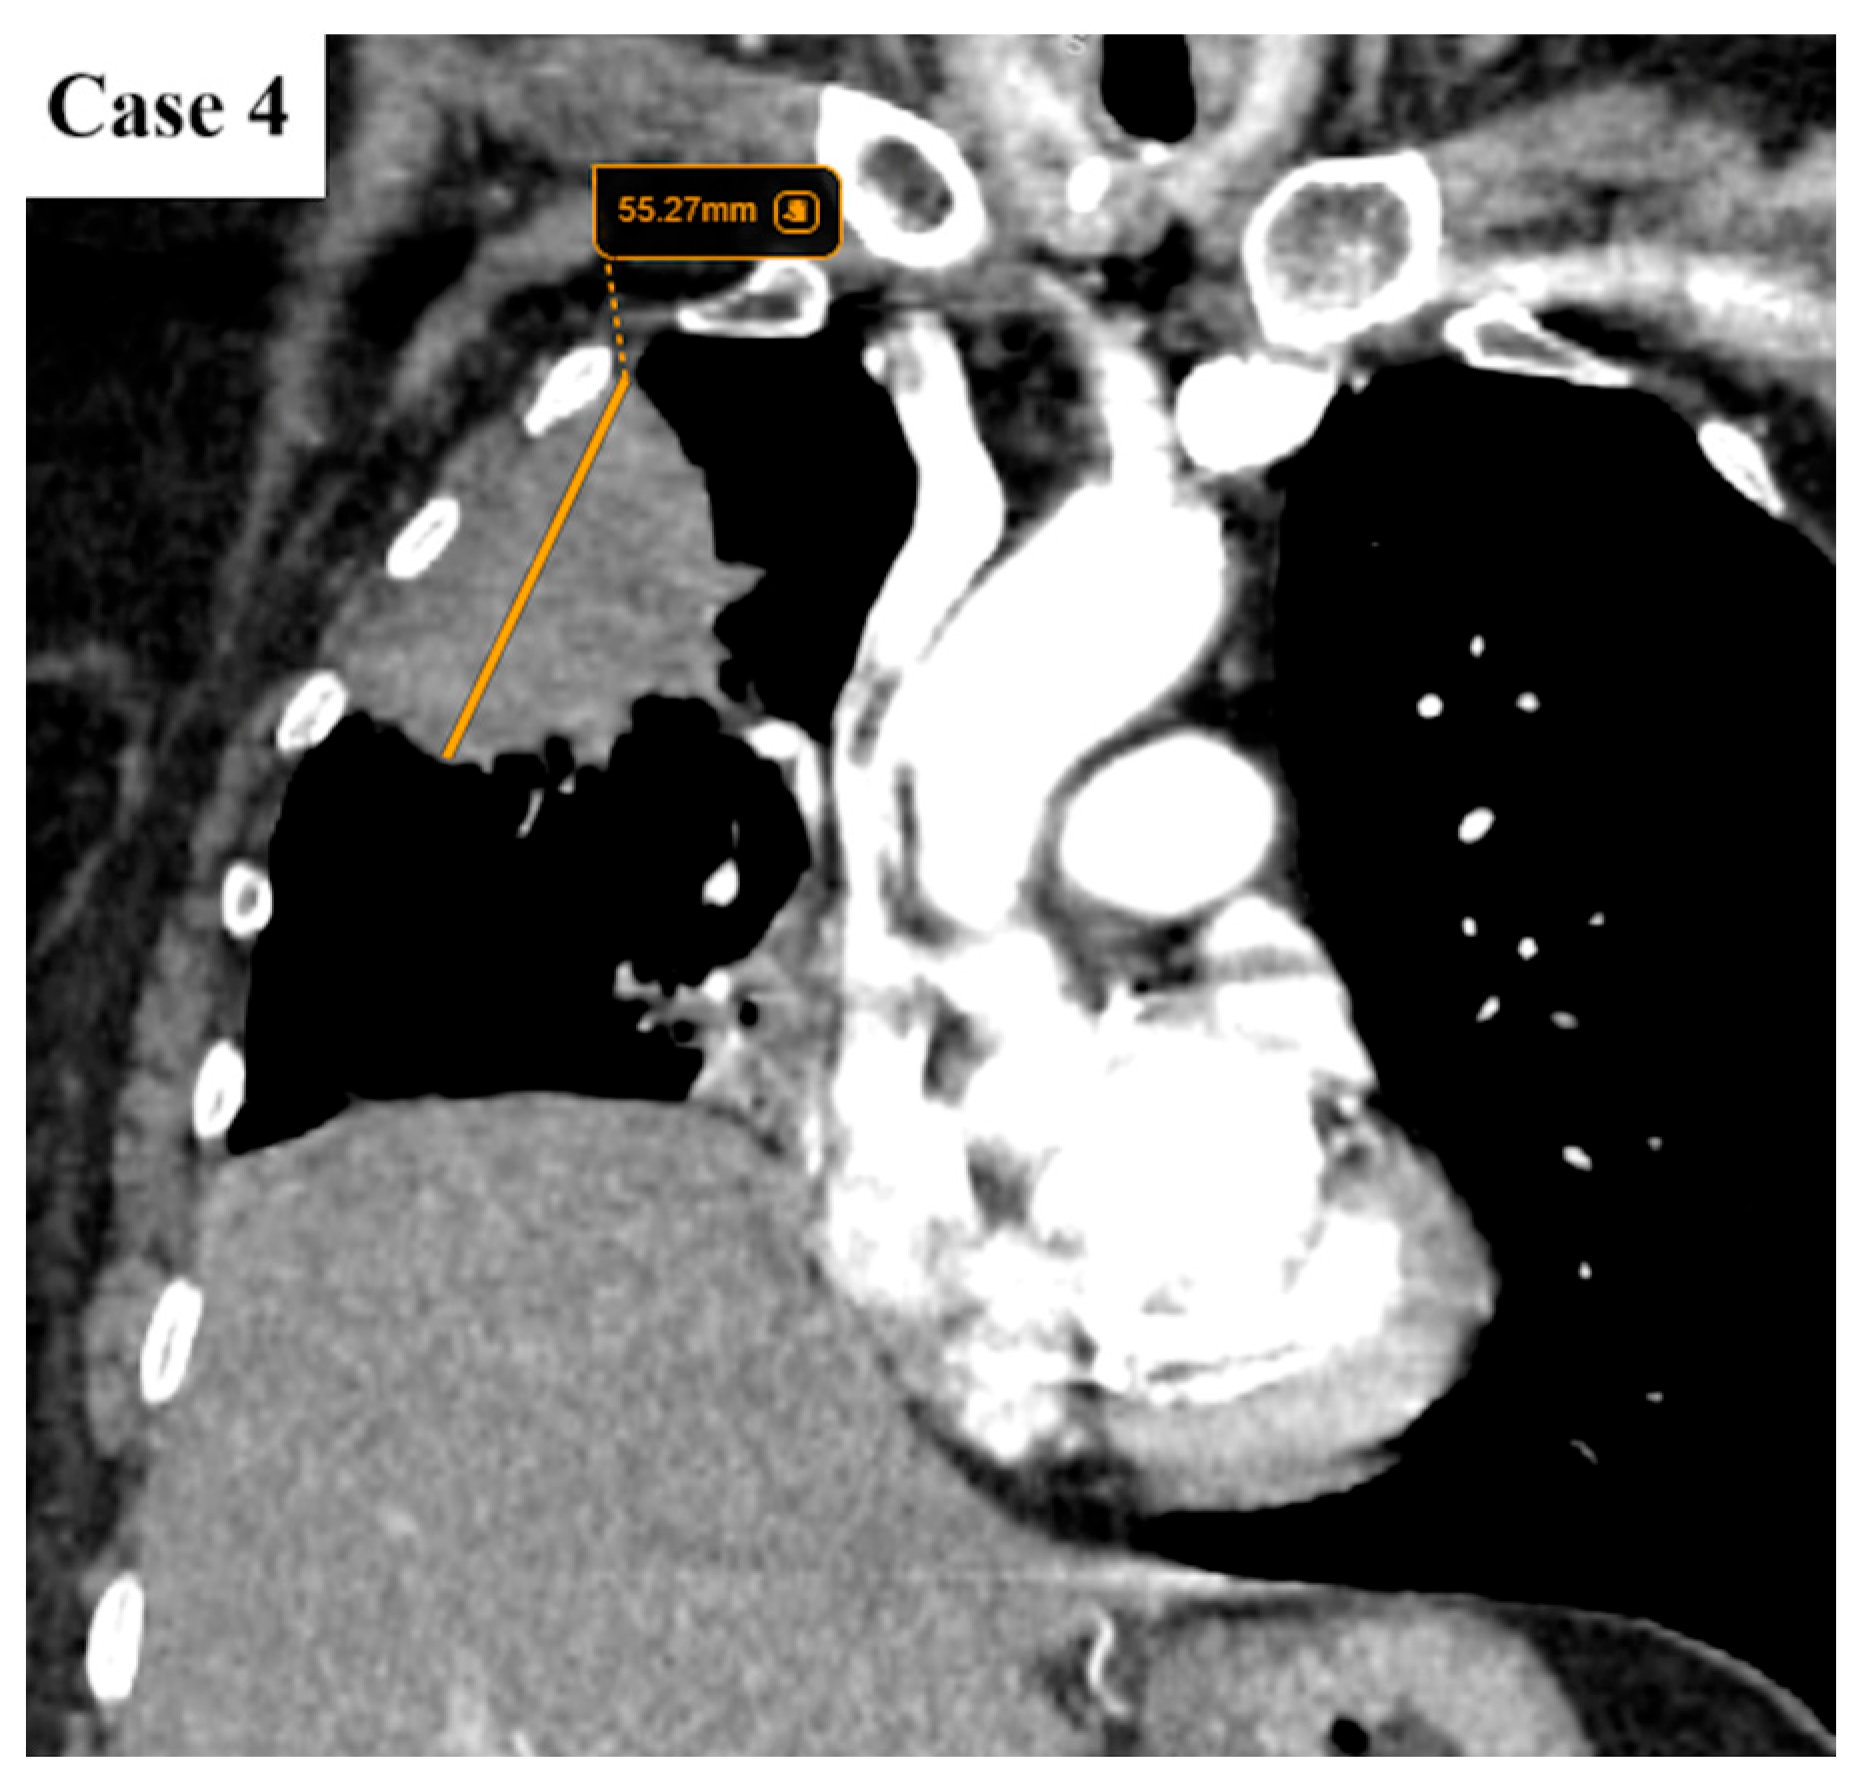

| Tumor size (cm) | Median 4.2 (IQR 2.6–5.9) |

| Imaging features | Spiculated margins: 88% Central necrosis: 38.4% Cavity: 10.4% Lymphangitic spread: 43.2% |